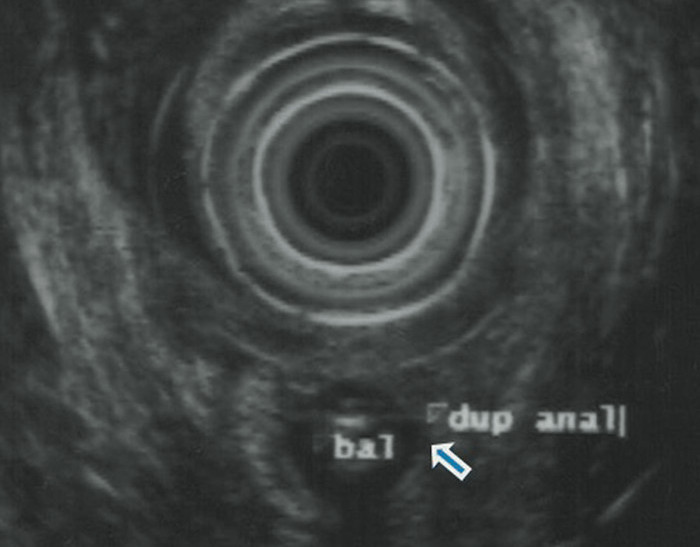

De acuerdo con el periódico, la paciente –no identificada– acudió al centro médico por sufrir abscesos en su parte trasera. Al examinarla, los especialistas se llevaron la sorpresa de encontrar no uno sino dos agujeros anales, en una evidente y rara malformación del tracto digestivo.

Fisiológicamente, la materia fecal pasa a través del canal anal, que se conecta directamente con el recto, donde se almacenen los residuos antes de dejar el cuerpo. En teoría, la mujer podría haber sido capaz de excretar a través de ambos canales. No obstante, los médicos determinaron que su segundo canal, de tan solo 3 centímetros de profundidad y un centímetro de ancho, no estaba vinculado con la pared rectal, aunque se hallaba separado del canal principal sólo por la piel.